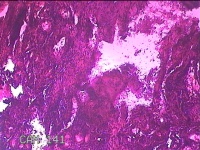

左侧鼻腔新生物

性别

女

年龄

43岁

临床诊断

1.慢性鼻窦炎 2.鼻息肉 3.鼻中隔偏曲 4.鼻腔粘连 5.变应性鼻炎

一般病史

鼻塞、脓涕3月余。’

标本名称

大体所见

灰白暗红色不规则肿物1.3x0.3x0.2cm一个,表面糜烂,内有少许骨质。

图4